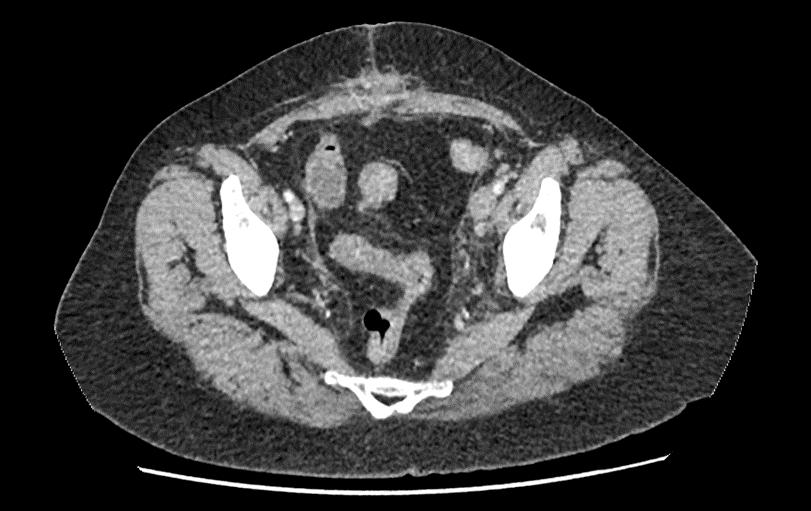

Create a flipbook